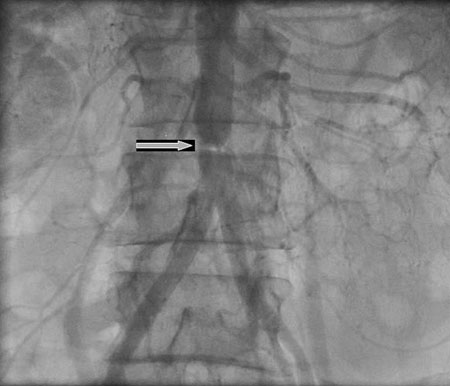

Abdominal coarctation

N. Pal, D. McEneaney. BMJ Case Reports, 2009